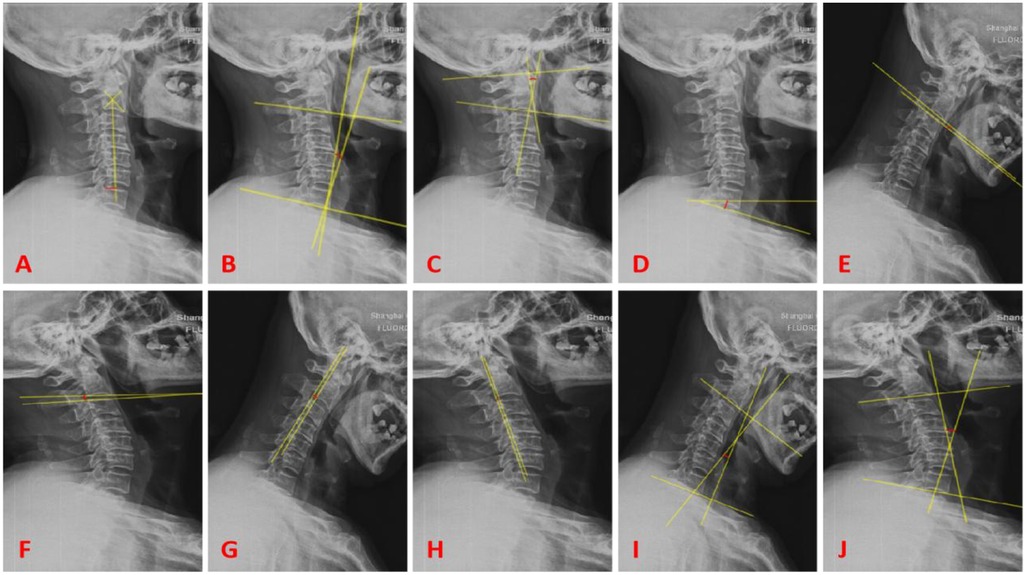

Preoperative and postoperative cervical spine lateral, flexion-extension, CT, and MRI images are obtained. The PACS 3.0 system software is used to measure the following sagittal parameters on cervical x-ray images: C0-2 Cobb angle, C2-7 sagittal vertical axis (SVA) in millimeters, C2-7 Cobb angle, T1-Slope, range of motion (ROM) of the cervical spine, displacement of the C2 vertebral body (measured as the distance between the posterior edge of the C2 vertebral body and the posterior edge of the C3 vertebral body on flexion-extension x-ray images in millimeters), and the angle of motion at the C2/3 level (measured as the difference in angle at the C2/3 level on flexion-extension x-ray images). Two physicians independently measure the imaging parameters twice using the described method. The average value of the measurements is taken as the final measurement data. The assessors are blinded to the study content. Please refer to Figure 1 for specific measurement methods.

Figure 1

X-ray images labeled A to J show lateral views of the cervical spine with varying alignments of yellow lines indicating different angles and points of measurement. Each image highlights different anatomical regions or angles, assisting in assessing spinal alignment and curvature.

Figure 1. (A) Represents C2-7 SVA (red line); (B) represents C2-7 cobb angle (red line); (C) represents C0-2 cobb angle (red line); (D) represents T1-slope (red line); (E,F) represent the difference in angle (red line) for the motion angle of C2/3 gap; (G,H) represent the difference (red line) for the displacement of C2 vertebral body; (I,J) represent the difference (red line) for ROM.